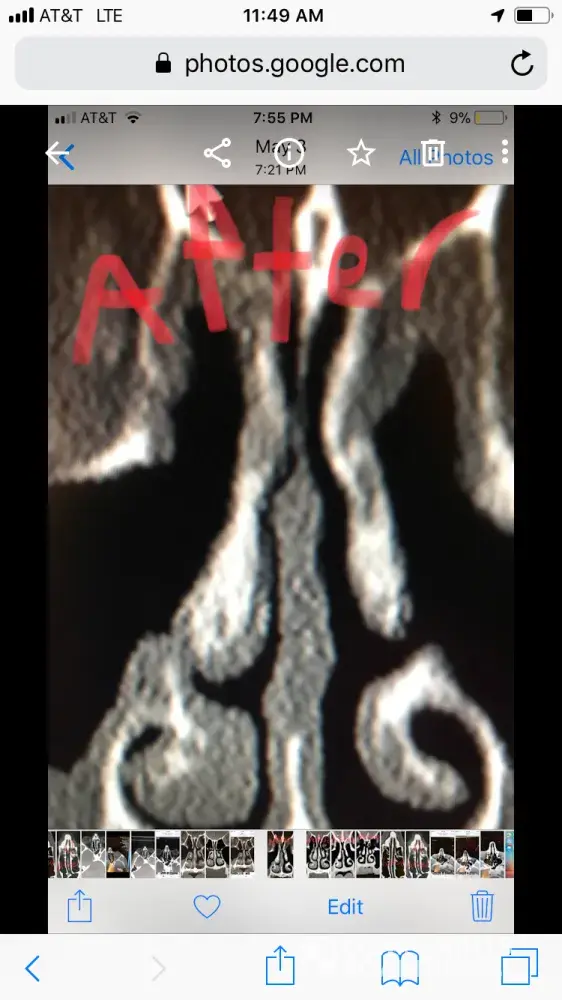

For people reading this, I have included x-ray images of the inside of my nose, before and after my surgery with him. As you can see from these images, my nasal airway was equally open on both sides, before surgery, and the septoplasty didn't need to be done. By performing it, he severely narrowed the right side of my nasal airway.

Dr Raviv performed two surgeries on me: endoscopic sinus surgery (where they widen the sinus passages), and septoplasty (where they straighten the septum). The septoplasty, however was completely unnecessary, and severely narrowed the right side of my nasal airway. For people reading this, I have included x-ray images of my sinuses, before and after my surgery with Dr. Raviv. As you can see from the surgery, my airway was much more open, and equal on both sides, before my surgery with him.